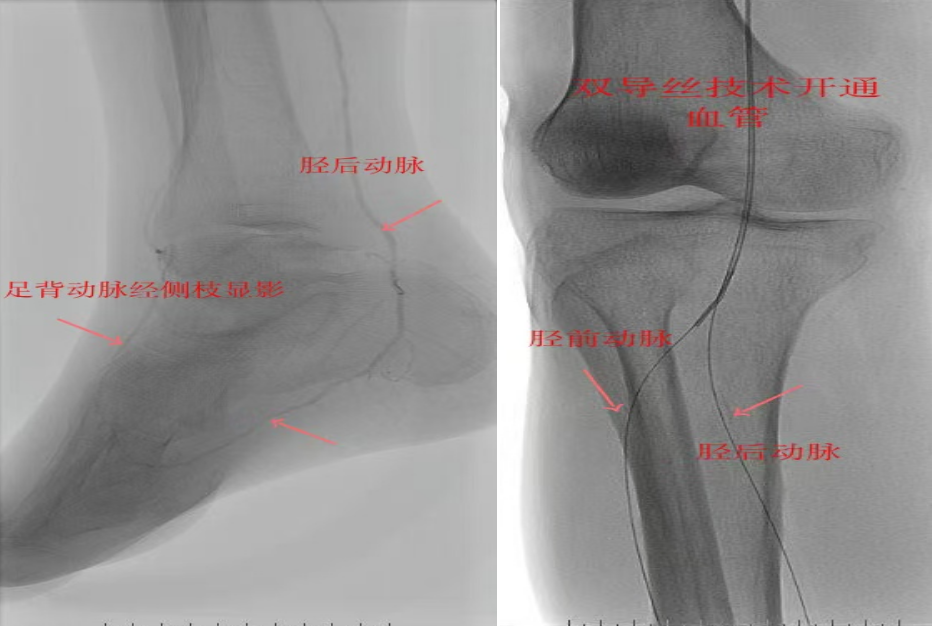

78岁男性患者,糖尿病合并高血压、脑梗塞,右足持续疼痛伴冰凉发绀3个月。入院CTA显示其右侧股浅动脉全程闭塞,膝下三支动脉均闭塞。医疗团队在局部麻醉下,再次巧妙应用“逆向开通技术”,经胫后动脉——足底弓逆向开通足背动脉及胫前动脉。术后患者右足皮温即刻回升,疼痛消失。术后结合中药外治(换药、熏洗、去腐生肌膏外敷)加速创面愈合,患者已顺利出院。

影像检查:CTA显示右侧股浅动脉全程闭塞,膝下三支动脉(胫前、胫后、腓动脉)完全闭塞。

两例患者共同凸显三大高难度治疗挑战:1.患者高龄且基础病复杂;2.血管全程多节段闭塞、钙化程度严重;3.常规顺向开通路径已被完全阻断。团队果断采用远端逆行穿刺技术,在纤细的足踝部血管建立治疗通道,实现“逆向破冰”。

“逆向开通操作技术”就像在复杂的血管迷宫中反向找“出口”。介入血管外科杨彦林副主任形象地比喻道,“该操作技术突破了传统顺向开通的技术局限,为濒临截肢的晚期糖足患者提供了宝贵的保肢新选择。”目前该方案已成为我院治疗复杂下肢动脉病变的常规手段。